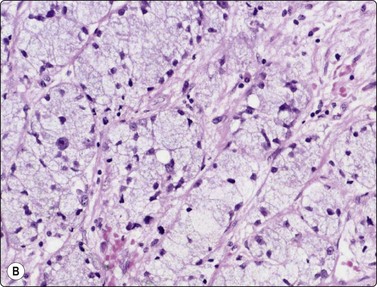

Oncocytoma (Fig. 4.45)13,22,123

image image

Fig. 4.45 Oncocytoma

Multilayered aggregates of cohesive oxyphil cells showing some nuclear enlargement and anisokaryosis but bland nuclear chromatin (A, MGG, HP; B, Pap, HP).

Criteria for diagnosis

Cohesive, multilayered aggregates of oncocytic cells with small, regular nuclei,

Absence of fluid, debris and lymphoid cells.

Problems and differential diagnosis

Variants of oncocytoma,

Other tumors with oncocyte-like cells (acinic cell carcinoma),

Distinction from Warthin’s tumor,

Multifocal oncocytic hyperplasia,

Malignancy.

Clear cell and eosinophilic variants of oncocytoma have been described.124

Cells with abundant cytoplasm from non-oncocytic tumors can resemble oncocytes in MGG-stained preparations. Acinic cell carcinoma has been mentioned above. Cells from mucoepidermoid tumors and from adenocarcinoma sometimes also have this appearance.

Oncocytomas may be cystic and their relationship to Warthin’s tumors is then uncertain. In general, cyst fluid with debris, oncocytes and lymphoid cells indicate a Warthin’s tumor, especially if the oncocytes lie in flat sheets.

Multifocal oncocytic hyperplasia of salivary gland may suggest oncocytoma in FNB smears.125

The cytologic findings in malignant oncocytic neoplasms have been described in a small number of cases.22 See also Oncocytic salivary duct carcinoma, page 70.